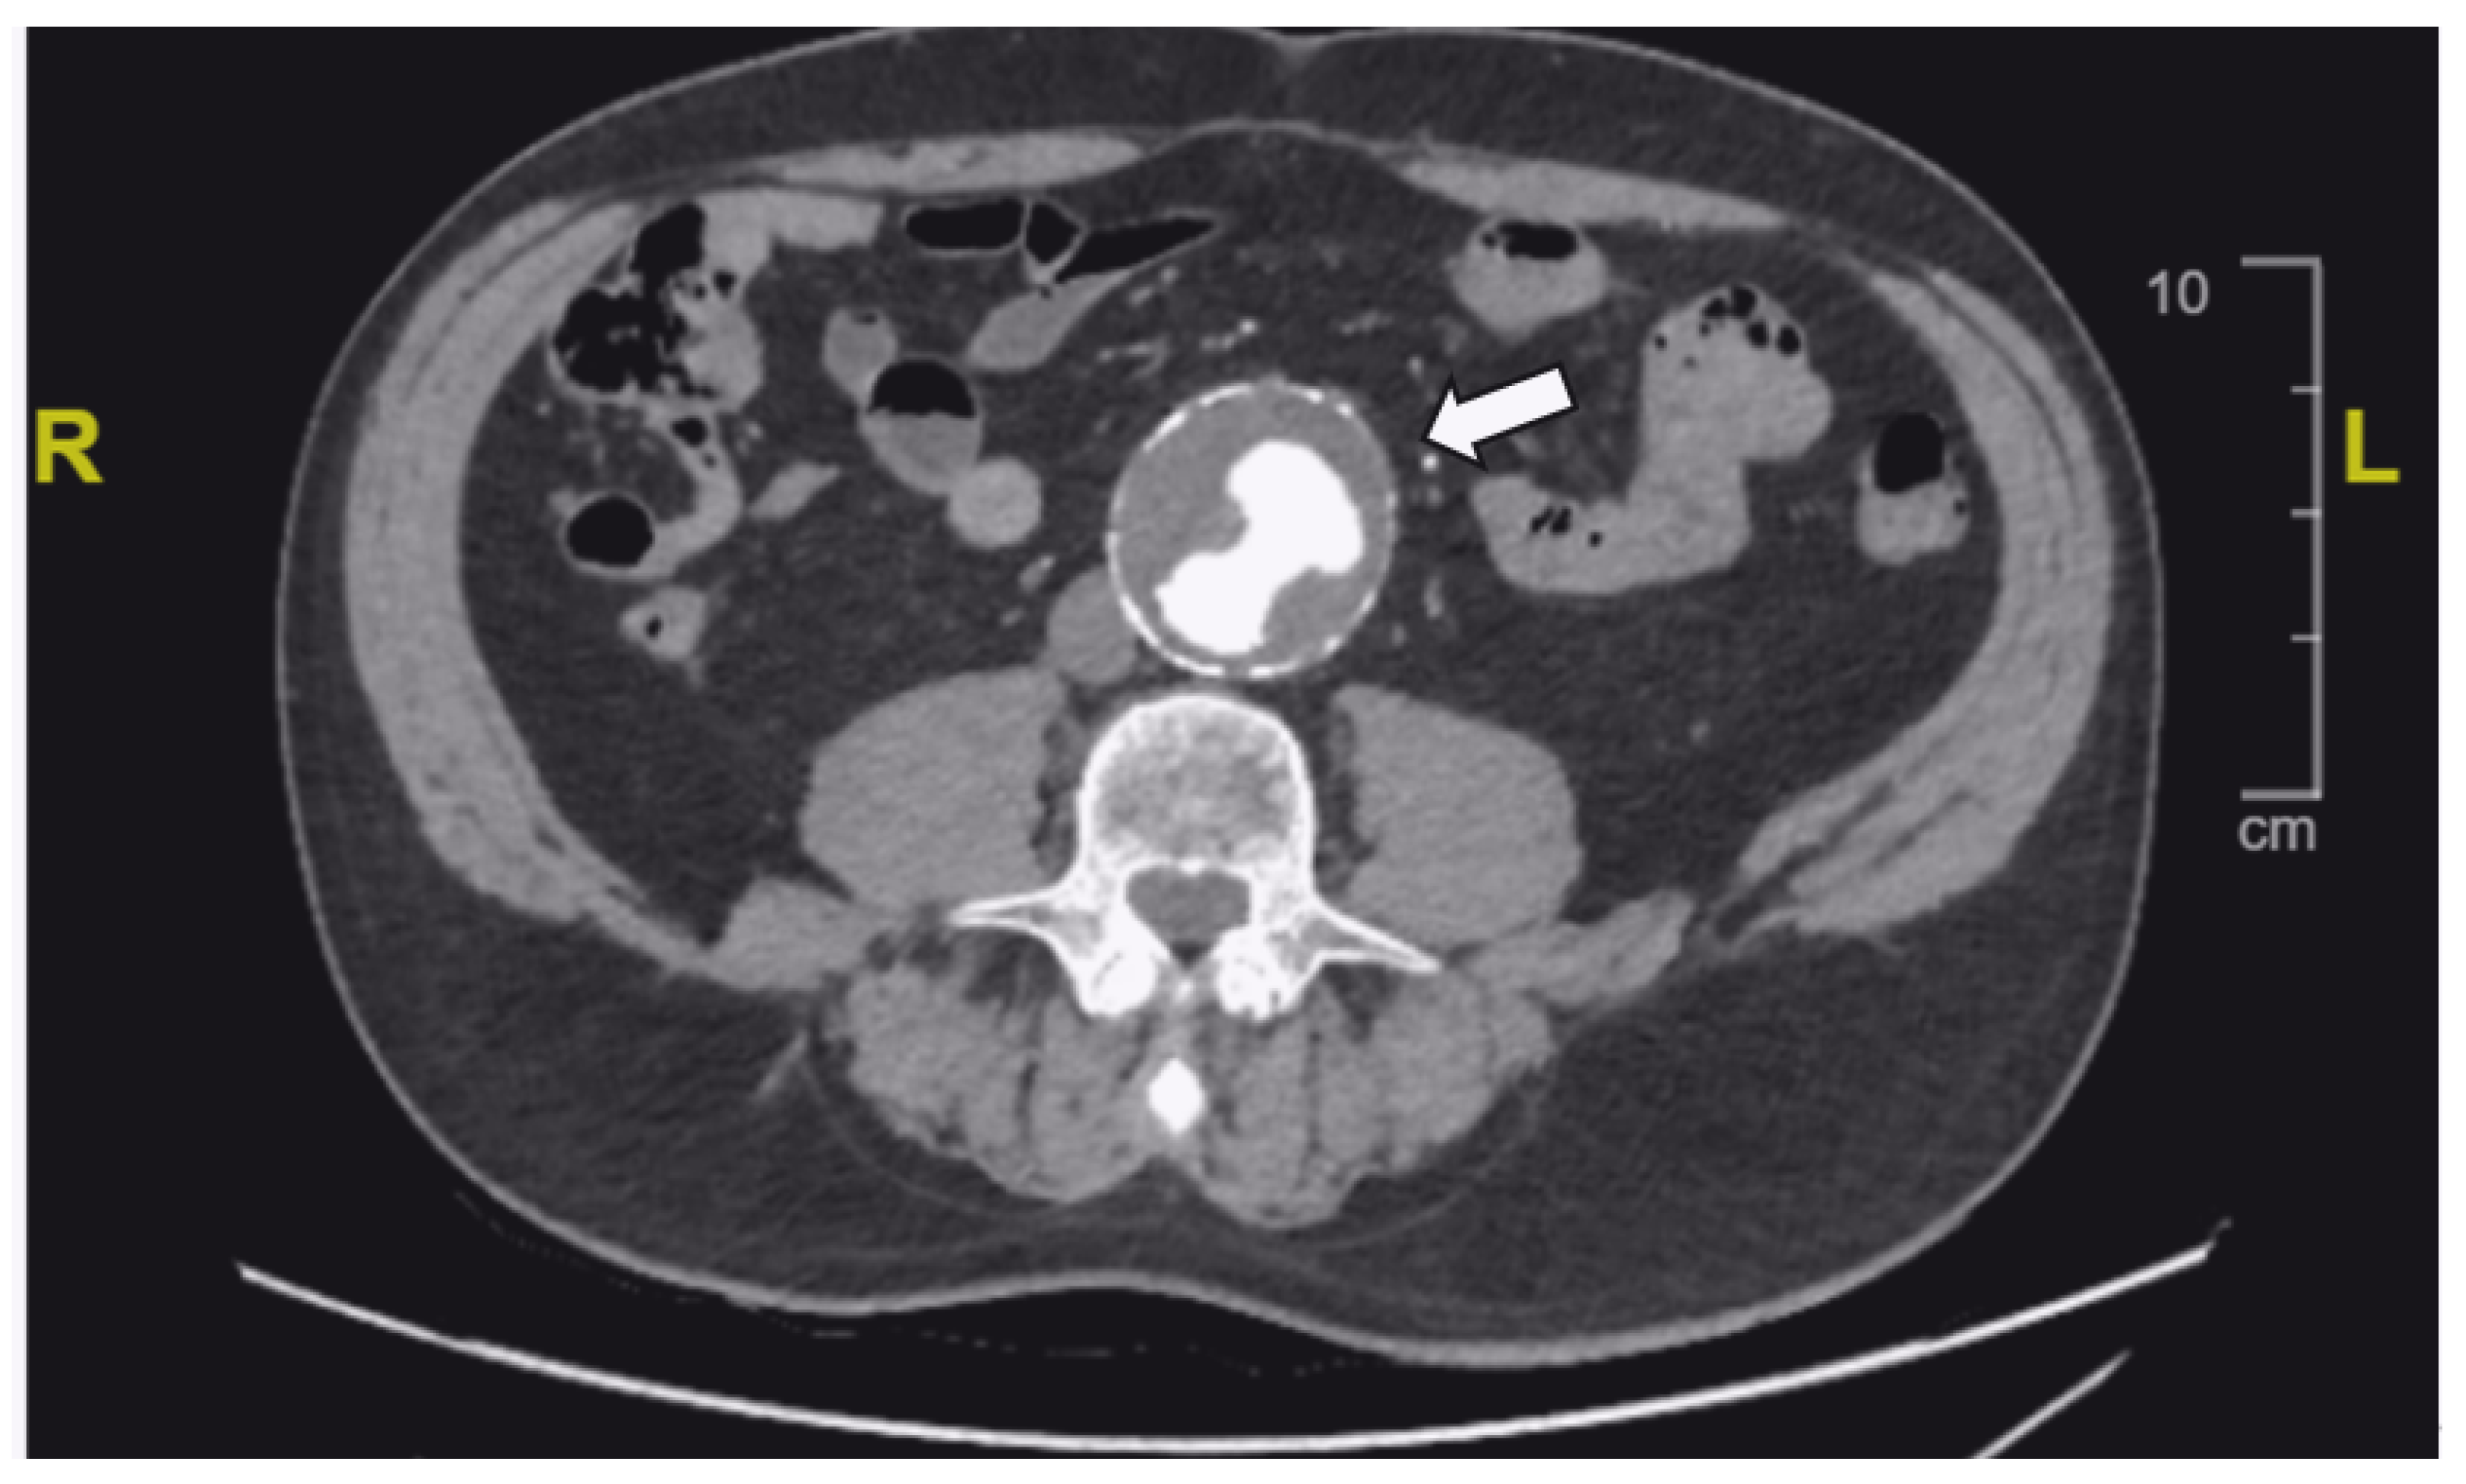

2. Case Report